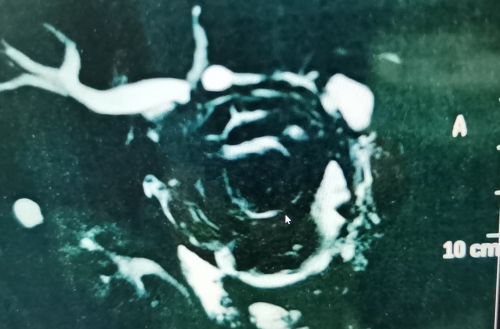

磁共振显示桥袢部位有结石影。

惊恐的李先生经多方打听,找到捷克论坛 肝胆胰微创外科尹新民主任医师处就诊。尹新民教授详细询问病史并仔细查阅CT及磁共振影像资料发现,李先生无连续肝外胆管,肝内有积气,据此推断他曾做过胆肠内引流手术,此次应是“桥袢巨型结石”引发右上腹疼痛。

“桥袢是连接肝门胆管和十二指肠的一段长约4560cm的肠管,形状似桥,连接胆道和肠道,起到引流胆汁的作用”,尹新民教授表示,桥袢结石多见于胆肠内引流术后,肝内结石下坠,以结石和胆肠吻合口缝线为中心,胆泥常年淤积而形成巨大结石,从而阻塞胆道,造成梗阻性胆管炎。如发展为重症,将危及患者生命。